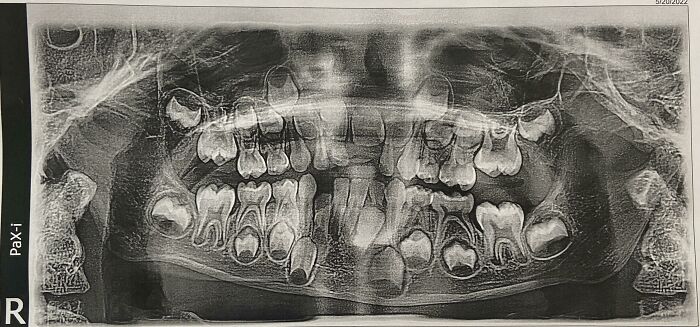

#5 Röntgen zubov môjho 6-ročného dieťaťa